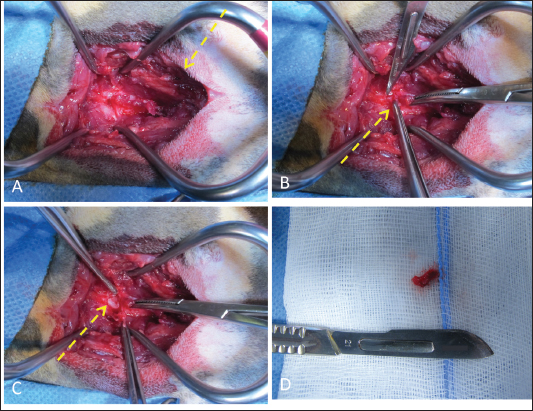

The cat was placed in sternal recumbency with the neck gently flexed in a neutral position. The skin was aseptically prepared, and a midline skin incision was made from the atlas to the level of the seventh cervical vertebra to explore the cervical region. The epaxial muscles showed evidence of blunt trauma without signs of direct laceration (Fig. 4A). The nuchal ligament was split longitudinally, and the cervical vertebrae spinous processes were identified. The multifidus muscle was elevated from the spinous processes to expose the dorsal lamina and perform the fourth and fifth cervical vertebrae skeletonization. The bone fracture was then identified at the dorsal lamina’s caudal margin of C4, caudal to the spinous process. The caudal fragment was grasped and elevated with bone forceps (Fig. 4B). The periosteum and ligamentum flavum lateral and caudal to the fragment were then severed and gently removed with a scalpel blade. The spinal cord below the fragment showed no gross alteration or signs of contusion (Fig. 4C). After removing the bone fragment, both fentanyl and ketamine CRIs were gradually tapered, and the cat remained normotensive with a normal heart rate until the end of the surgery. Once the surgical field was irrigated and adequate hemostasis was confirmed, the fascia, subcutaneous tissue, and skin were sutured in a routine fashion.

Fig. 4. Surgical approach to vertebral fracture of C4 through a dorsal cervical approach. (A) Once the surgical access was performed, the epaxial muscles showed gross evidence of blunt trauma (yellow dotted arrow). (B) The fourth and fifth cervical vertebrae were skeletonized to evidence the bone fracture. Then, the caudal fragment was grabbed, elevated, and removed, cutting the flavum ligament (note the bone fragment between the forceps, yellow dotted arrow). (C) The uncompressed spinal cord was visualized after the bone fragment was removed (yellow dotted arrow).